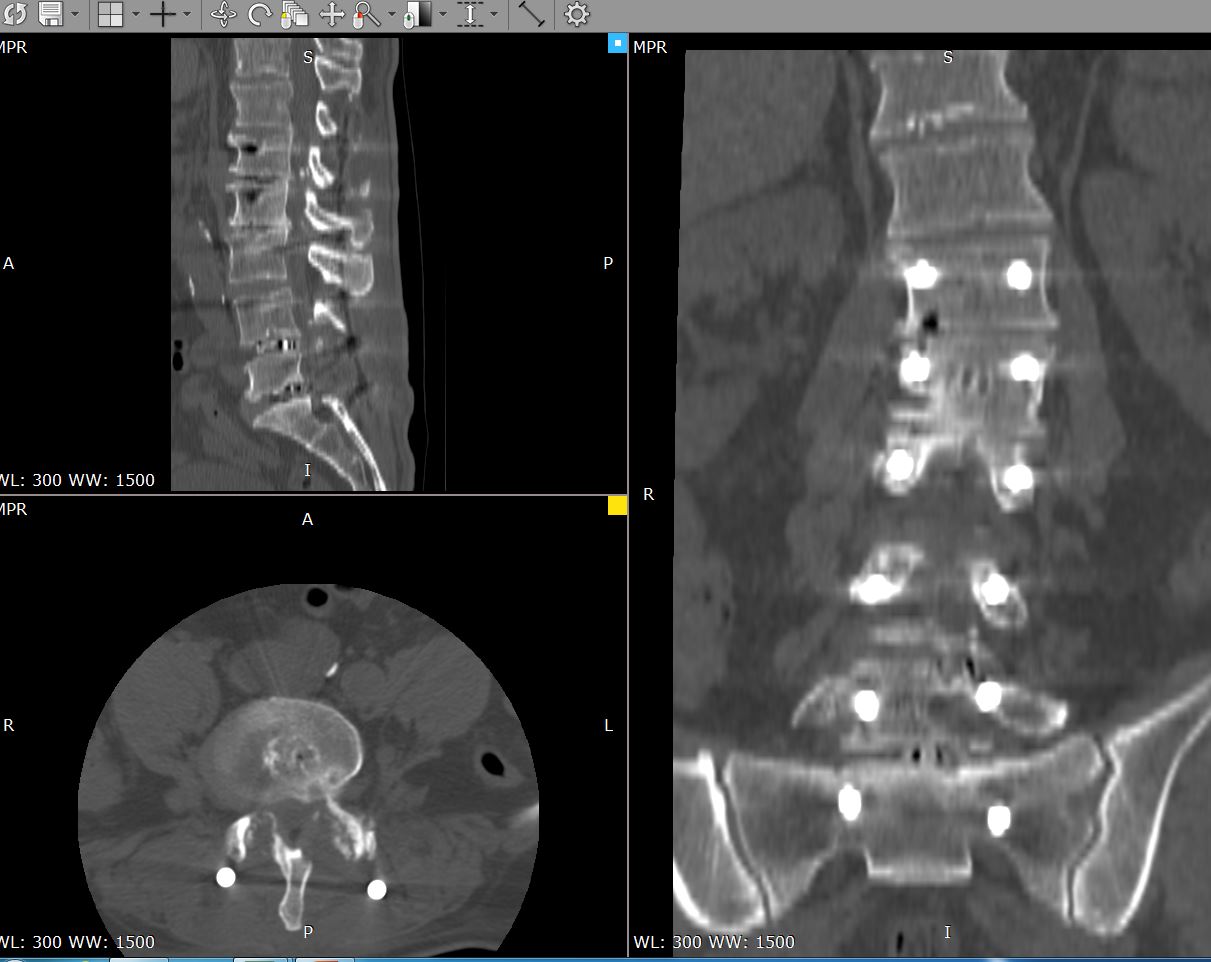

Рис - Многоуровневый стеноз МРТ до операцииРис - Многоуровневый стеноз КТ после операции

Операция при стенозе может выполняться несколькими способами:

декомпрессионная ламинэктомия — удаляют часть позвоночной дуги;

стабилизация — после ламинэктомии закрепляют позвоночный столб металлическими скобами;

микрохирургическая декомпрессия — устраняют стеноз и укрепляют позвоночник, сохраняя способность к сгибанию и разгибанию;

микродискэктомия — удаляют грыжу, если она спровоцировала сужение канала.

Вид оперирования, что сказывается на цене, врач подбирает индивидуально на основании причины и клинической картины заболевания.